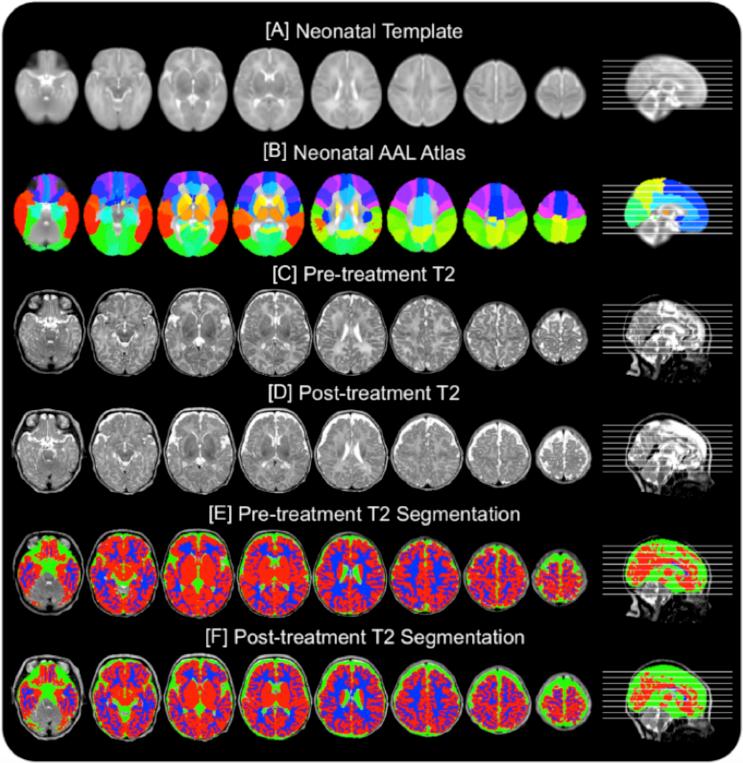

We report the case of a former 33-week premature infant born with long-gap esophageal atresia that underwent complex perioperative critical care (Foker process) requiring prolonged post-operative sedation and whom presented with incidental subdural hematoma. Rs-fMRI data was acquired (at 1-month corrected age) and (at 2.25-months corrected age) complex perioperative care. We evaluated resting-state functional connectivity (RSFC) using graph theory to explore the complex structure of brain networks.

A transient increase in head circumference coincided temporally with lifting of sedation and initiation of sedation drugs weaning, and qualified for hydrocephalus (93%) but not macrocephaly (>95%). RSFC analysis identified networks spatially consistent with those previously described in the literature, with notable pre-post-treatment qualitative differences in correlated and anticorrelated spontaneous brain activity.

头围的短暂增加在时间上与镇静解除和镇静药物减量开始相吻合,符合脑积水标准(93%)但不符合巨头症标准(>95%)。RSFC分析确定的网络在空间上与先前文献中描述的网络一致,治疗前后相关和反相关的自发脑活动存在显著的定性差异。